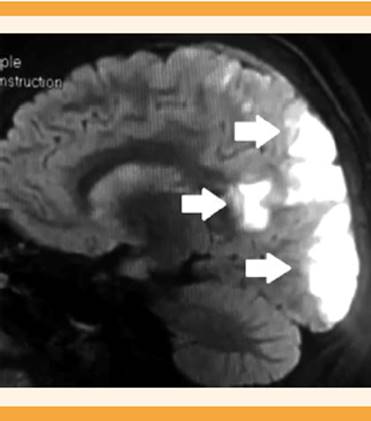

La resonancia magnética nuclear reportó: trombosis de la vena cortical frontal izquierda que condicionó un evento agudo isquémico del lóbulo frontal ipsilateral (Figuras 1y2), trombosis parcial de la vena sagital superior en el tercio medio y vena cortical parietal izquierda (Figura 3), hiperintensidades puntiformes de la sustancia blanca, con patrón vascular no reciente, turbulencia del flujo del seno lateral derecho. Sin datos de síndrome de encefalopatía reversible posterior.

Figura 1 Resonancia magnética nuclear: corte sagital en fase T2 con evento agudo isquémico del lóbulo frontal condicionado por trombosis de vena cortical frontal izquierda.

Figura 2 Resonancia magnética nuclear: corte transversal en fase T2 con evento agudo isquémico del lóbulo frontal, condicionado por trombosis de vena cortical frontal izquierda sin datos de síndrome de encefalopatía reversible posterior.